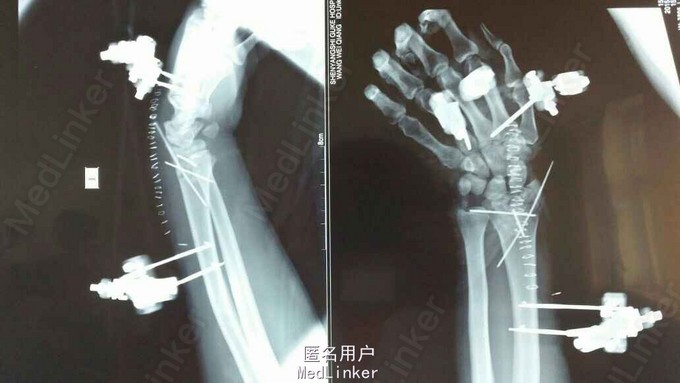

患者于2015年8月18日从高处坠落(约7米)伤及双碗,肿胀,畸形,活动受限。

双碗畸形明显,肿胀明显,可见明显皮下淤血,压痛阳性,可触及明显骨察感及骨察感,左手有明显正中神经压迫症状。

诊断:双尺桡骨远端粉碎性骨折 治疗:入院后,给予手法复位夹板固定,左手神经症状明显缓解,给予对症治疗,消肿后,于2015年8月27日行手术治疗。

请问大家,对于这种骨折是行外架+克氏针固定好,还是钢板固定好?